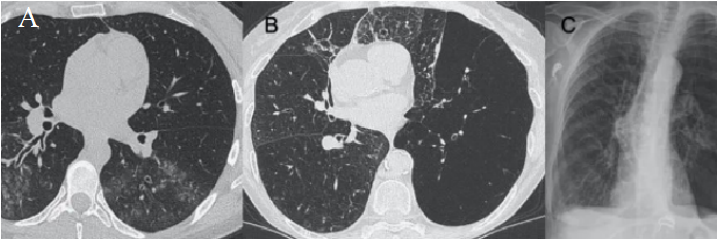

病毒性肺炎是由各种呼吸道病毒感染引发的肺实质炎症,容易并发呼吸衰竭,常见于幼儿(<5岁)和年龄>50岁的成人。WHO数据显示:社区获得性肺炎(CAP)中病毒性肺炎占20%~40%,在ICU中比例稍高,为30%~40%。常见病毒性肺炎的病原体包括流感病毒、鼻病毒、呼吸道合胞病毒、腺病毒、人偏肺病毒、巨细胞病毒、冠状病毒等。病毒性肺炎的常见影像学特征如下:图1所示为COVID-19的高分辨率CT(HRCT):在急性期,图1A为双肺弥漫性磨玻璃影(GGO),图1B为小叶周围型,图1C和D表现为亚急性间质性肺炎,GGO减少,主要为胸膜下局灶性实变和小叶间/小叶内间质增厚。图2A-C显示了一例与COVID-19间质改变相似的甲型流感病例:GGO主要分布在胸膜下和双侧,呈小叶周围性分布。图2D为同一患者的仰卧位胸片,可见弥漫性肺间质受累。图3A-D为一例H1N1相关肺炎并发急性呼吸窘迫综合征(ARDS)的影像,可见弥漫性、双侧GGO以及牵拉性支气管扩张。图4A显示了一例急性腺病毒肺炎,具有典型的多灶性和大叶GGO,图4B-C显示其导致的长期后遗症——Swyer–James综合征的表现。图5所示为一例疱疹病毒性肺炎,可见双侧分布呈斑片状的GGO(主要位于两肺上叶)。一项基于对美国大规模人群分析的前瞻性多中心研究显示,病毒性肺炎的患病率和发病率随年龄而异,其累积发生率约为22%。研究纳入2222例儿童,其中66%(共1472例)报告有病毒感染,在155例(7%)病例中发现病毒和细菌合并感染。事实上,呼吸道病毒、腺病毒和人偏肺病毒在5岁以下儿童中比较常见。在同一研究的2259例成年人患者中,只有853例(38%)患者检测到病原体,530例(23%)患有病毒性肺炎,59例(3%)发现合并感染。